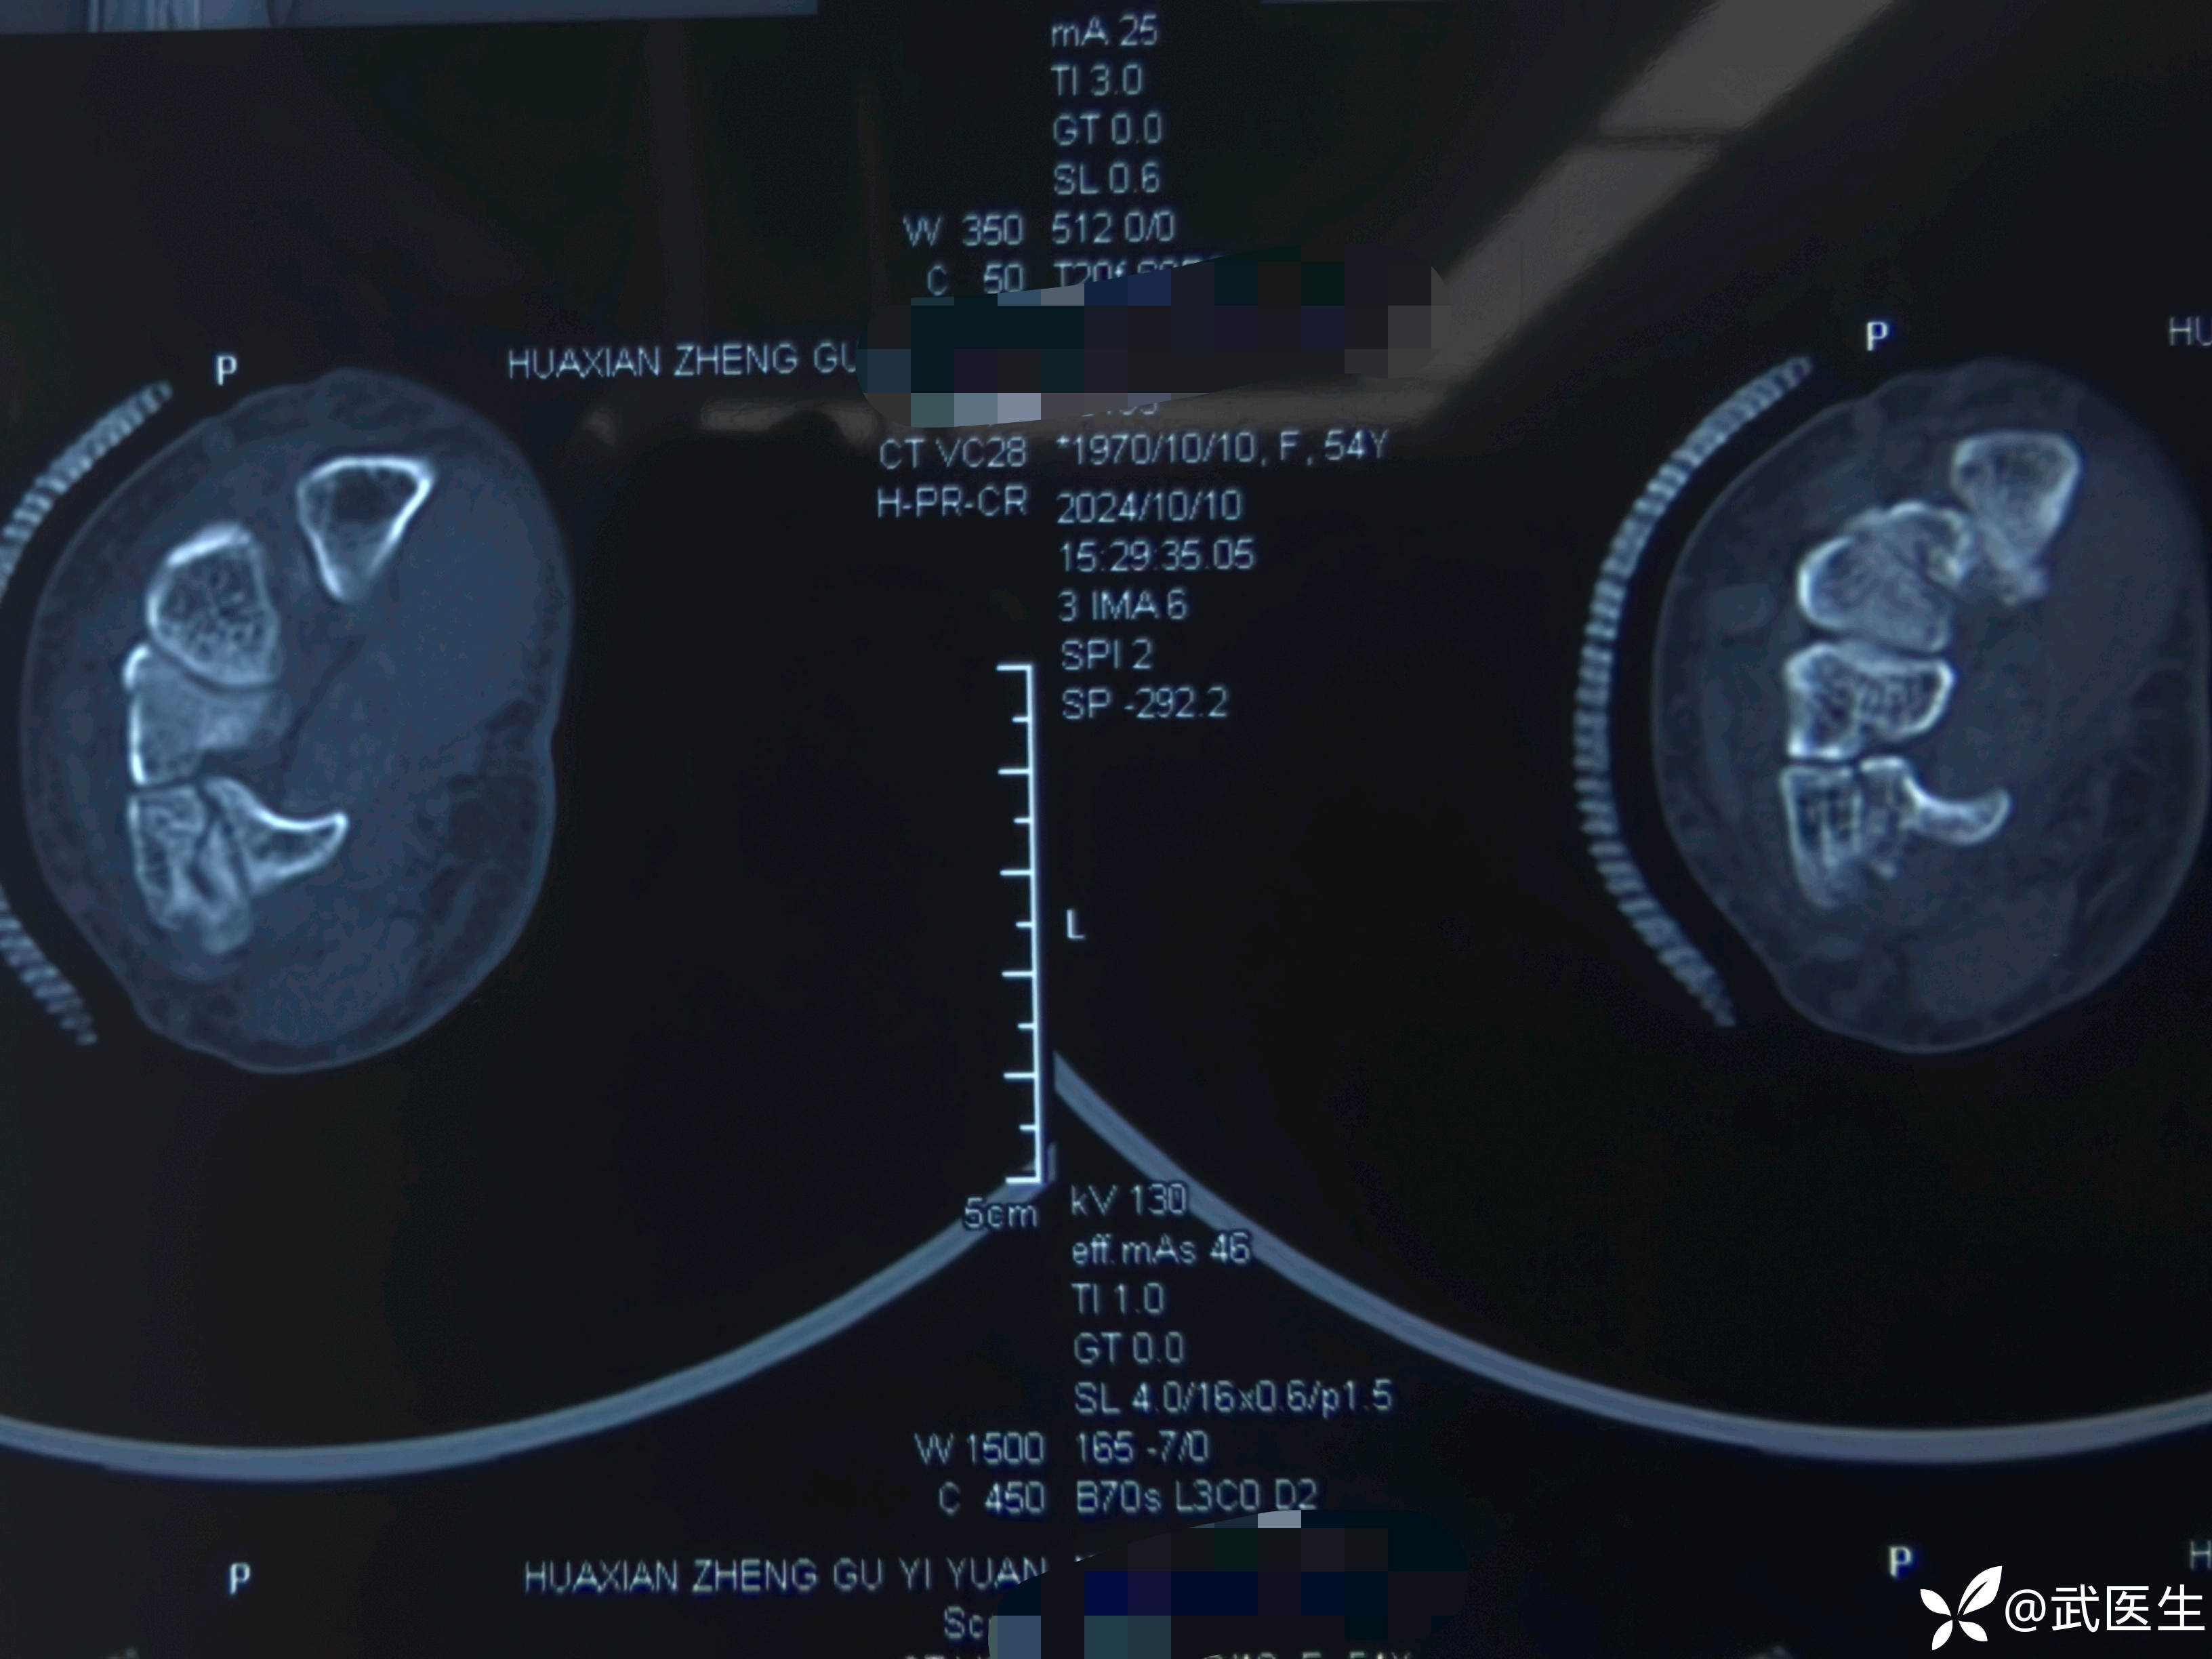

影像学检查如下

腕关节片子系外院带来

【临床诊断】:右肱骨外科颈四部分骨折脱位,左桡骨远端骨折伴桡腕关节半脱位。钩骨骨折。头面部软组织损伤。